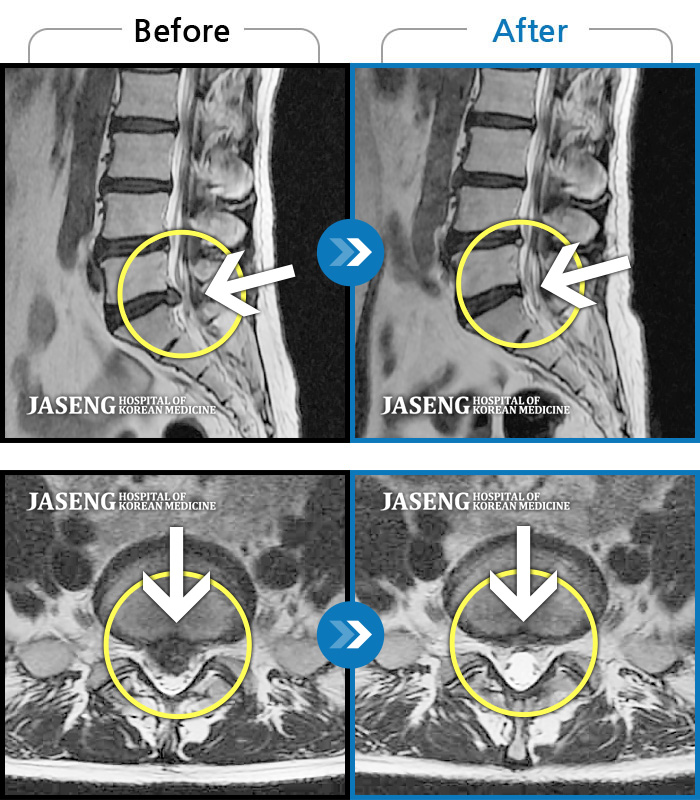

[뱸] 19.11.28~25.05.06